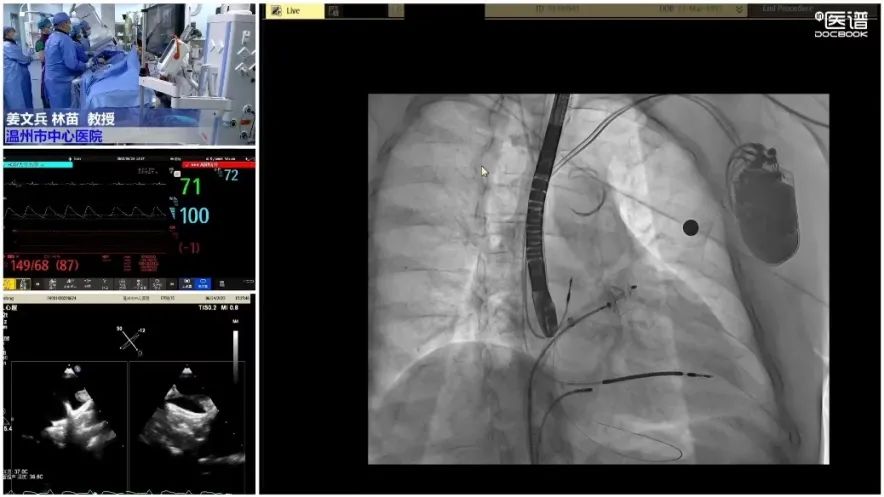

经过完善的术前检查及准备,姜文兵院长、林苗教授带领介入导管室医护人员、超声科陈颖团队、麻醉科李宇主任团队组成的多学科团队,密切配合完成手术。本次首例开展与国立台湾大学附属医院蔡佳醍教授连线交流,并通过医院“定理”微创医学学术周转播共同交流学习。

患者全麻后进行左心耳封堵术,在左心耳DSA造影及超声检查下,观察左心耳为菜花型,开口约23mm,锚定区约22mm,选择25mm(固定盘25mm/封堵盘32mm) Amulet左心耳封堵器。

食道超声评估左心耳封堵完全,牵拉稳定,无残余分流,完美释放。手术非常成功。

封堵过程用时仅约40分钟,也显示出Amulet预装式左心耳封堵器的操作便利性,有效缩短手术时间,患者症状得到缓解,身体康复良好。